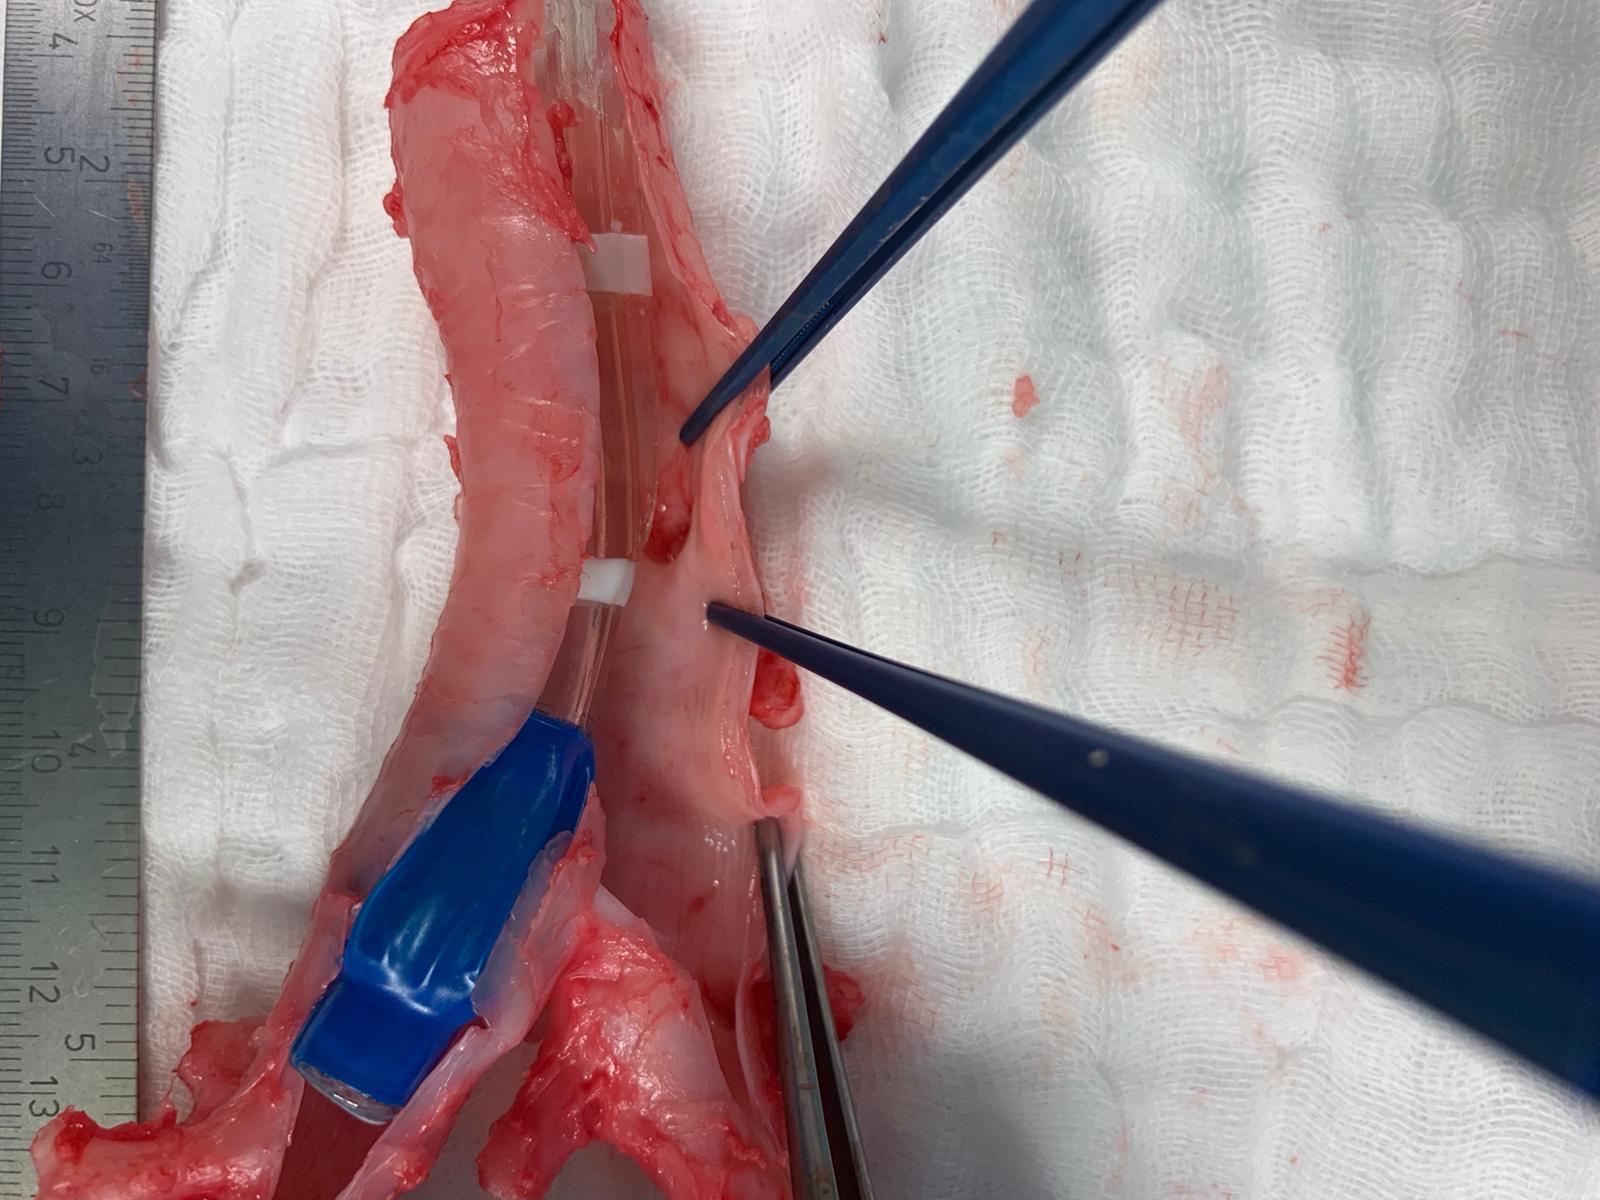

Pictures:

Im Oktober 2017 wurde in unserer OP-Gruppe der Hybrid-OP in Betrieb genommen. Dieser Herz-OP-Saal ist mit einer uniplanaren Fluoroskopie-Anlage, einem „high-end“ Echokardiographiegerät und hochauflösenden Monitoren ausgerüstet. Der Hybrid-OP wird von der Herzchirurgie, Kardiologie, Gefäßchirurgie und Interventionellen Radiologie genutzt.

Zur Steuerung der Interventionen werden Fluoroskopie, transösophageale Echokardiographie und Hämodynamik auf großen, hochauflösenden und für alle gut einsehbaren Monitoren wiedergegeben.

Während TAVIs in leichter Sedierung durchgeführt werden, benötigen andere Interventionen eine Allgemeinanästhesie: Transapikale oder trans-subclavia TAVI, transkatheter edge-to-edge repair der Mitral- und Trikuspidalklappe, transkatheter Mitralklappen- und Trikuspidalklappenersatz oder extra-anatomische bi-cavale Klappenimplantation (TricValve). Bei den herzchirurgischen transkatheter Eingriffen wird das Echo-Guidance von Mitarbeiter:innen unserer Abteilung bewerkstelligt.

Stentimplantationen in den großen Arterien (EVAR, TEVAR) in Kooperation zwischen Interventioneller Radiologie und Gefäßchirurgie oder Herzchirurgie werden meist in Allgemeinanästhesie durchgeführt.